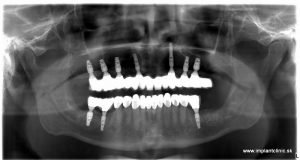

Na základe RTG a CT vyšetrenia náš hlavný implantológ MUDr. Marek Salka, odporučil pacientovi extrakcie nevyhovujúceho chrupu a následne celkovú rekonštrukciu hornej a dolnej čeľuste pomocou zubných implantátov s fixným keramickým oblúkom do vrchnej čeľuste a náhrada stoličiek v dolnom chrupe pomocou zubných implantátov a estetická úprava ostatných zubov pomocou zubných koruniek.

Plán ošetrenia pacienta Jakuba, a teda celková rekonštrukcia jeho chrupu, zahŕňal implantáciu 7 zubných implantátov do hornej čeľuste a 3 zubné implantáty do sánky. V spodnej čeľusti mal pacient na pláne ošetrenia naplánovaných ešte 10 zubných koruniek.

Nasledovala ešte kontrola záhryzu niekoľko dní po zákroku a o dva mesiace po implantácii nás pacient navštívil pre kontrolu a odobratie odtlačkov pre výrobu finálnych implantátových koruniek, ktoré sme nasadili pri pacientovej následnej návšteve u nás na klinike.